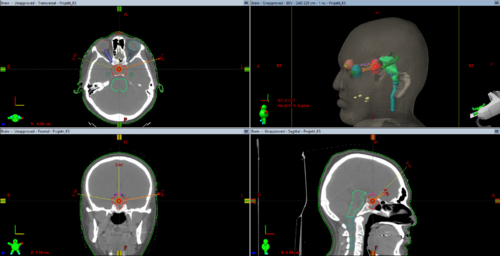

- 3 Felter: 2 laterale felter, drejet let anteriort (for at undgå hippocampus) og let superiort 10-15° (for at undgå at flugte med basis kranii). 1 felt med borddrejning 270° og en vinkel mellem 30° og 80° for at undgå at stoppe i hjernestammen.

Typisk 3-felts teknik vil se således ud: